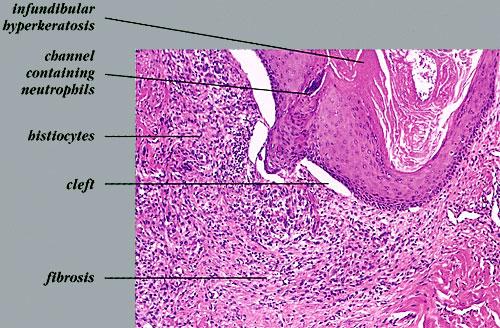

Atlas of skin histopathology

Acne vulgaris erythematous papule =العد الشائع